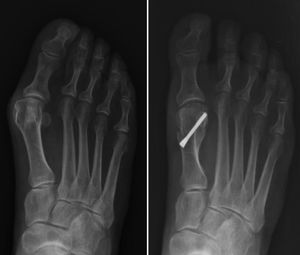

The osteotomy is fixed percutaneously with two compression screws from proximal to distal towards the metatarsal head. It should be noted that the proximal screw is the first placed, and this should pass through three cortices through the osteotomy for better screw fixation (Fig. 1).

The adductor tendon is then released percutaneously. The Kirschner wire is removed and a varus correction bandage is applied.